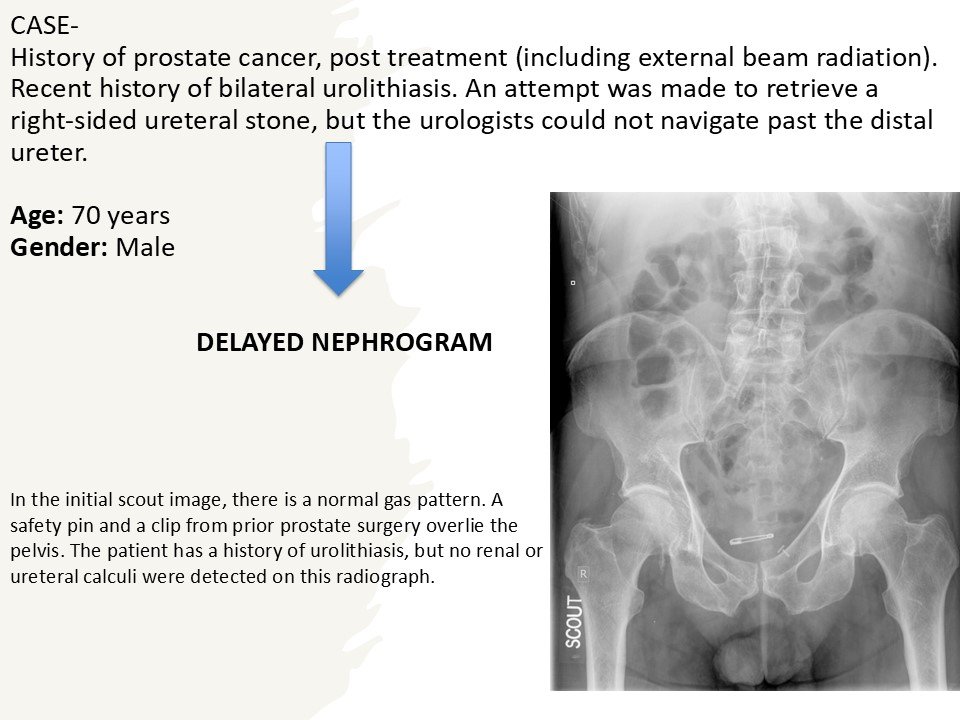

The right kidney and ureter were not visualized on intravenous urography until 60 min. The left kidney and ureter revealed normal.

On the 20 min post-void image there is opacification of the right kidney (delayed nephrogram), still without any contrast in the collecting system, compatible with high-grade obstruction of the right collecting system.

Severe Obstruction:

Non-visualized kidney.

Functional Role:

Demonstrates renal excretory function.

Delayed nephrogram suggests acute obstruction.

Current Status:

Largely obsolete.

Replaced by CT urography.